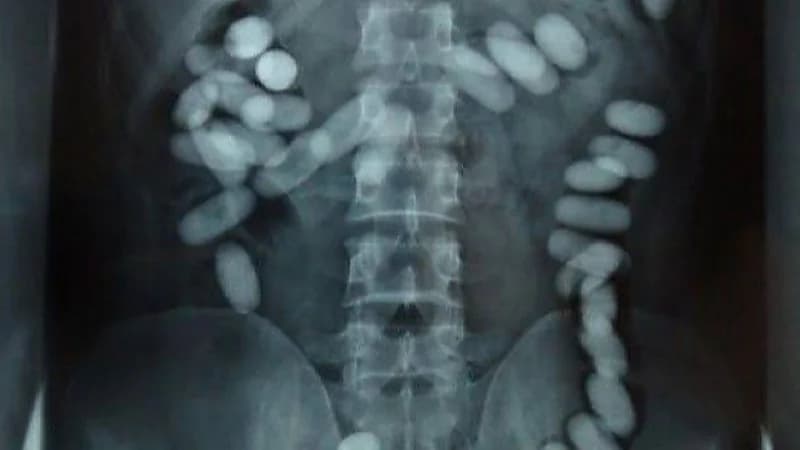

وعند القيام بتفتيش حقائب المتهم لم يتم العثور على أي مواد محظورة، لكن ظهرت عليه علامات التوتر والقلق، وأقر بحيازته لمواد مخدرة داخل أحشائه، فطُلب منه العبور من جهاز الكشف على المسافرين، وبالفعل تبين وجود جسم غريب داخل أحشائه فتم إبلاغ الشرطة بالواقعة.

وأفاد شرطي في التحقيقات، بأنه تم تحويل المتهم إلى المستشفى لإنزال ما داخل أحشائه، وتم تحويل المواد المشتبه فيها إلى المختبر الجنائي، حيث تبين أن المواد المضبوطة «ميفيدرون» المخدرة وتزن 73 جراماً.